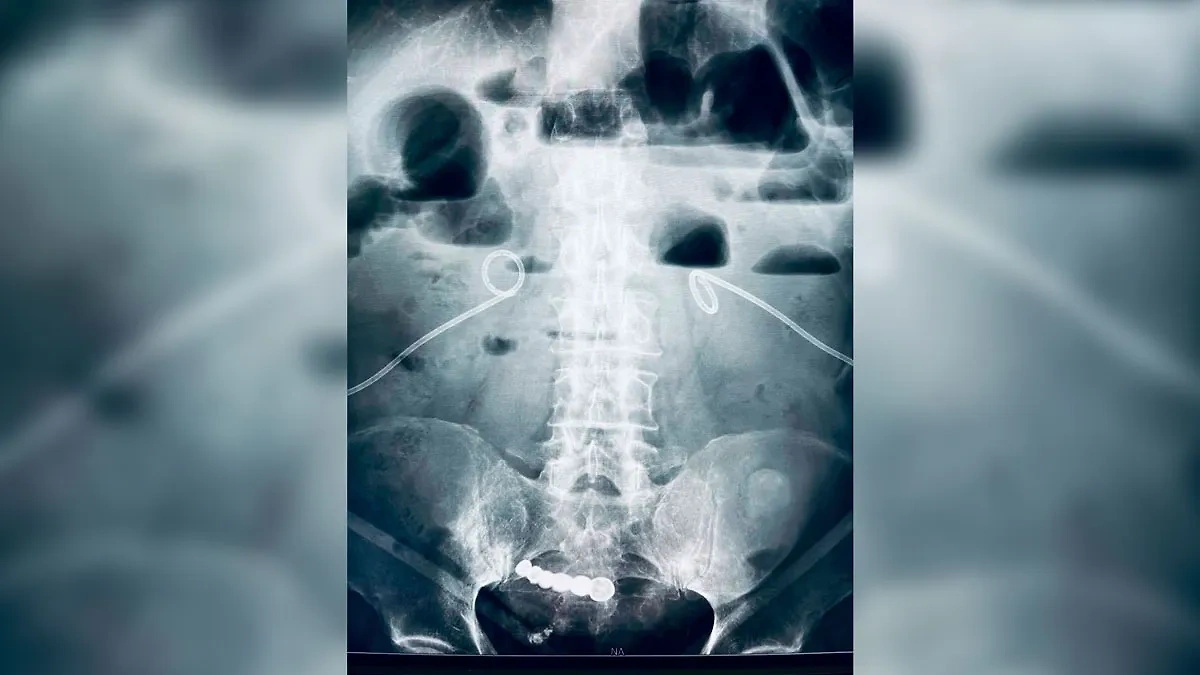

Рентген, на котором видно вставную челюсть в животе пациента. Фото © t.me / Беглов_Zdrav

"Кемеровчанин обратился в больницу с острой болью в животе. На рентгене врачи обнаружили "зубы". Выяснилось, что несколько лет назад дедушка проглотил вставную челюсть. Боли не было — и он не пошёл к врачам. Инородный предмет долгое время не доставлял никаких неудобств. Хирурги больницы удалили протез малоинвазивным методом. Пациент уже дома", говорится в публикации Беглова.